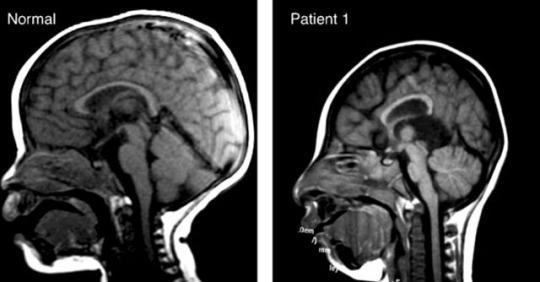

A 32 year old woman comes to your gynecological practice for a 20 week check-up and